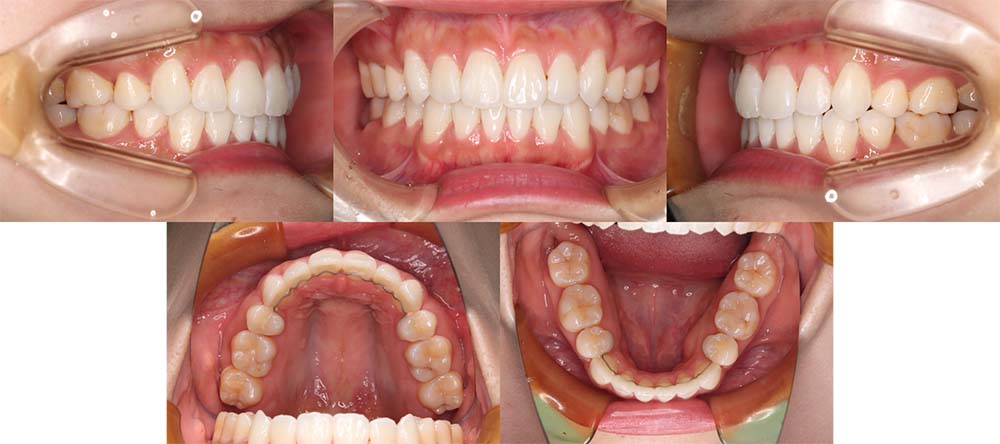

| 症例分類 | 叢生 |

| 診断名 | 上下叢生 |

| 主訴 | 八重歯と下の歯のガタガタが気になる |

| 年齢 | 24歳4ヶ月 |

| 性別 | 女性 |

| 抜歯部位 | 上下左右の第一小臼歯(4本) |

| 使用装置 | 上は裏側、下は表側のワイヤー装置 |

| 治療期間 | 2年8ヶ月 |

| 保定装置 | 固定式保定装置、取り外し式保定装置(8時間) |

| 費用 |

[検査・診断料] ¥49,500 [基本施術料] ¥1,056,000 [調整料] ¥5,500/回 [抜歯] ¥5,500/本 [保定装置] ¥55,000(税込) 抜歯や虫歯治療は他院にて費用が別途かかります。(抜歯¥4,000〜10,000/本)

上下叢生のため、上下第一小臼歯を抜去して上裏側下表側のハーフリンガルで治療しました。

顎間ゴムは治療期間の半年程度使用しましたが、協力度が良好だったためしっかり咬合することができました。

治療開始前にホワイトニングをしたこと、咬合力が強いためか装置の脱離が多く、予定より治療期間が伸びてはしまいました。